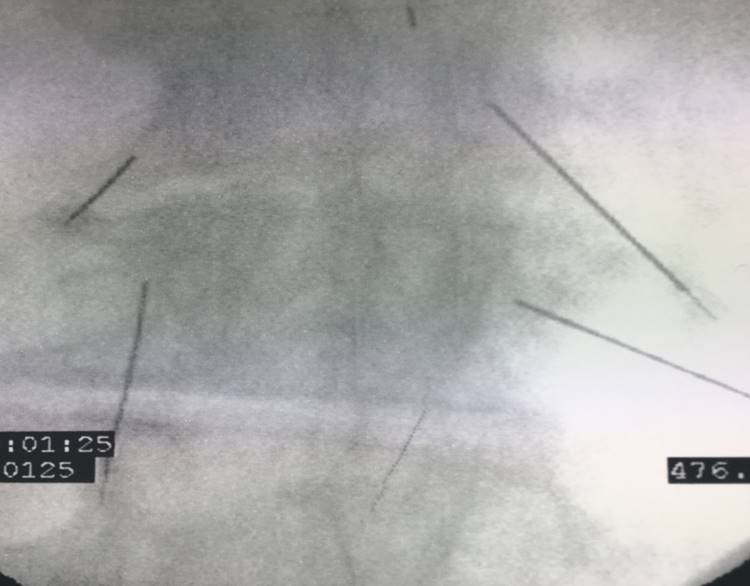

Εικόνα 9

Ακτινογραφία της Ο.Μ.Σ.Σ. – Υπό ακτινοσκοπικό έλεγχο έχουν τοποθετηθεί ειδικές βελόνες στις σπονδυλικές διαρθρώσεις (Facets) και έγινε έγχυση cocktail φαρμάκων τα οποία δρουν αναλγητικά.